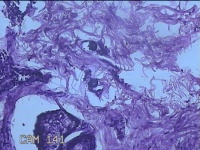

性别

男

年龄

23岁

临床诊断

右耳部肿物

一般病史

右耳前无痛性肿物20余年。

标本名称

大体所见

灰白暗红色肿物0.7x1.5x0.2cm一个,表面糜烂。

图4